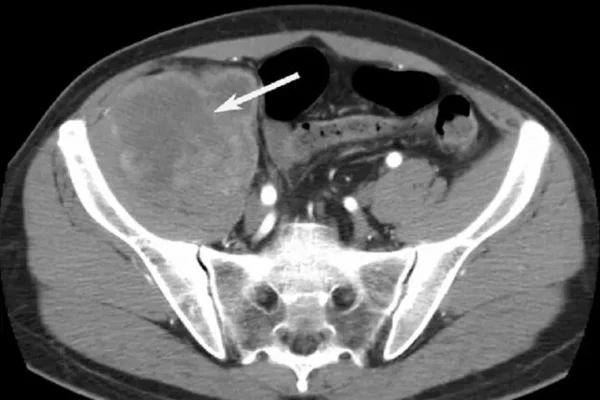

- Bilgisayarlı Tomografi